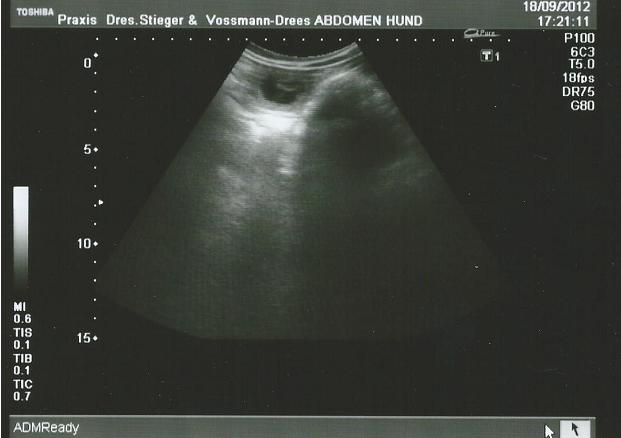

18.09.12

28. Tag

Heute ist der beste Zeitpunkt, um die Trächtigkeit per Ultraschall nachzuweisen.

!!!JUHU Es hat geklappt Inara ist trächtig!!!